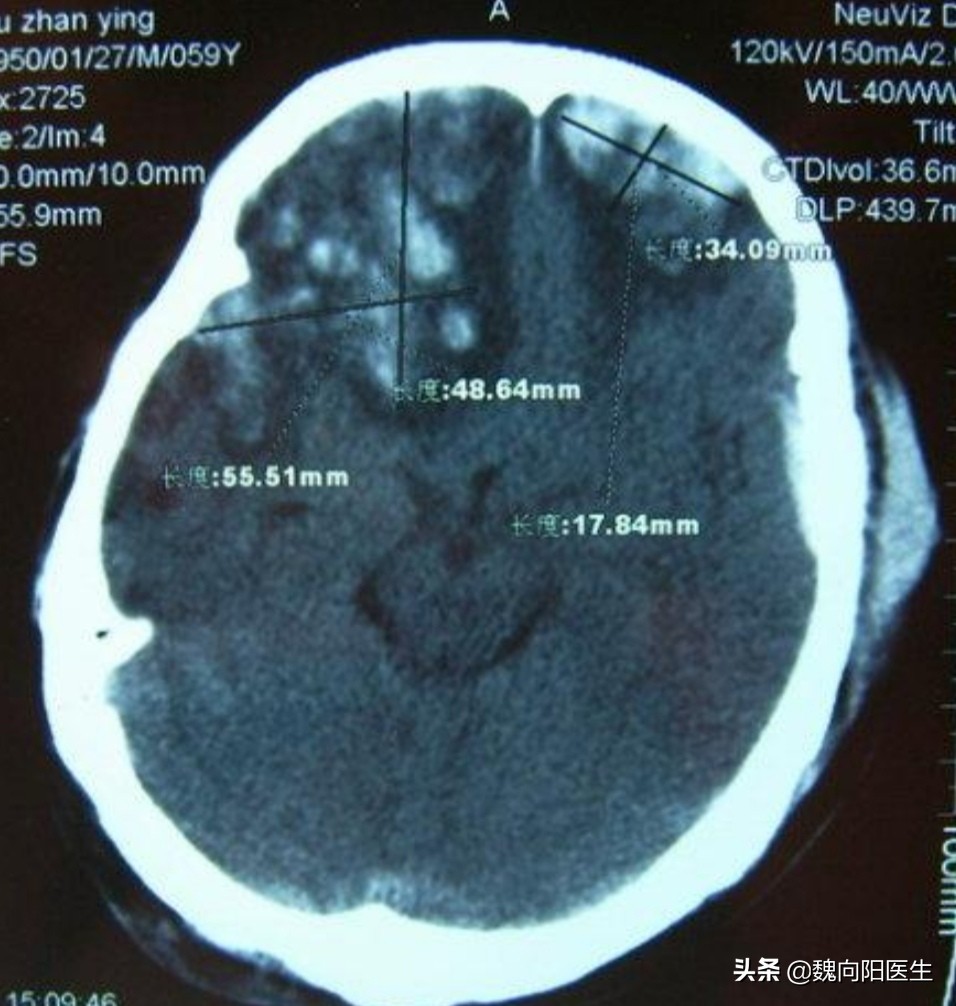

美国警察把老人用力推倒后,美国老人后退几步后摔倒在地?后脑勺着地,当时后脑勺就流血了,看摔倒的视频,应该是头部外伤不清。怀疑颅内应该也出血了。

一般撞到头部后脑勺,很多脑出血是发生在前额或前颅底部位。这叫做对冲伤。

早期出现脑额颞叶挫裂伤

对冲伤(contre-coup injury):头部受外力作用时,于着力处的对侧部位的脑组织发生损伤,称为对冲伤。对冲伤多见于头颅撞击外界物体而致伤者,少见于受打击致伤者,即减速运动多见。

由于前颅底骨头表面不光滑,且神经组织众多,在后枕部受到撞击后,导致脑组织在不光滑颅骨表面滑动,从而导致脑挫裂伤、硬膜下血肿或蛛网膜下腔出血可能。